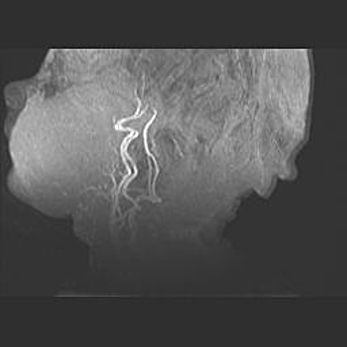

Церебральная ишемия II.

Возраст: 5 дней

Вес: 3400 г

Пол: женский

Окружность головы: 35 см

Срок гестации: 39 недель

Церебральная ишемия – это заболевание, характеризующееся недостаточностью (гипоксией) либо полным прекращением (аноксией) снабжения мозга кислородом по причине закупорки одного или нескольких сосудов. Это приводит к  что метаболическим расстройствам различной степени тяжести в тканях головного мозга, развитию коагуляционных некрозов и гибели нейронов.